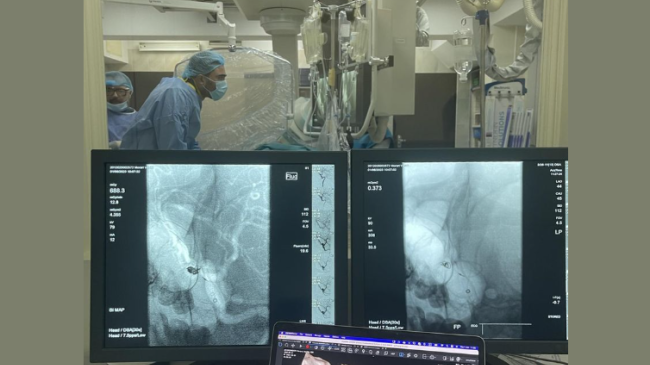

O echipă multidisciplinară de la Institutul de Medicină Urgentă, formată din neurochirurgi și chirurgi endovasculari, a salvat viața unui pacient de 25 de ani, diagnosticat cu hemoragie subarahnoidiană, cauzată de un anevrism rupt de artera comunicantă anterioară, anunță Ministerul Sănătății.

Anevrismul cerebral reprezintă dilatarea unui vas de sânge al creierului, ruperea căruia provoacă hemoragie, aceasta fiind o urgență medicală majoră, care în lipsa tratamentului se soldează cu consecințe tragice. Pentru tratarea anevrismului cerebral, medicii au recurs la tehnica minim invazivă de embolizare endovasculară. Aceasta presupune sigilarea anevrismului cu spirale, introduse prin arteră cu ajutorul unui tub, numit cateter.

Astfel, circulația sângelui la nivelul anevrismului a fost blocată, iar pacientul este înafara pericolului. După șapte zile de la intervenție tânărul în stare bună a fost externat la domiciliu.

Echipa care a efectuat intervenția: Victor Andronachi, șeful Departamentului de Neurochirurgie, Alexandru Andrușca, medic neurochirurg, Andrei Filioglo, medic neurolog intervenționist, Roman Smolnițchi, șeful Laboratorului Medicină Intervențională, Serghei Taran, medic anestezist, Irina Batarovschi, asistentă medicală.